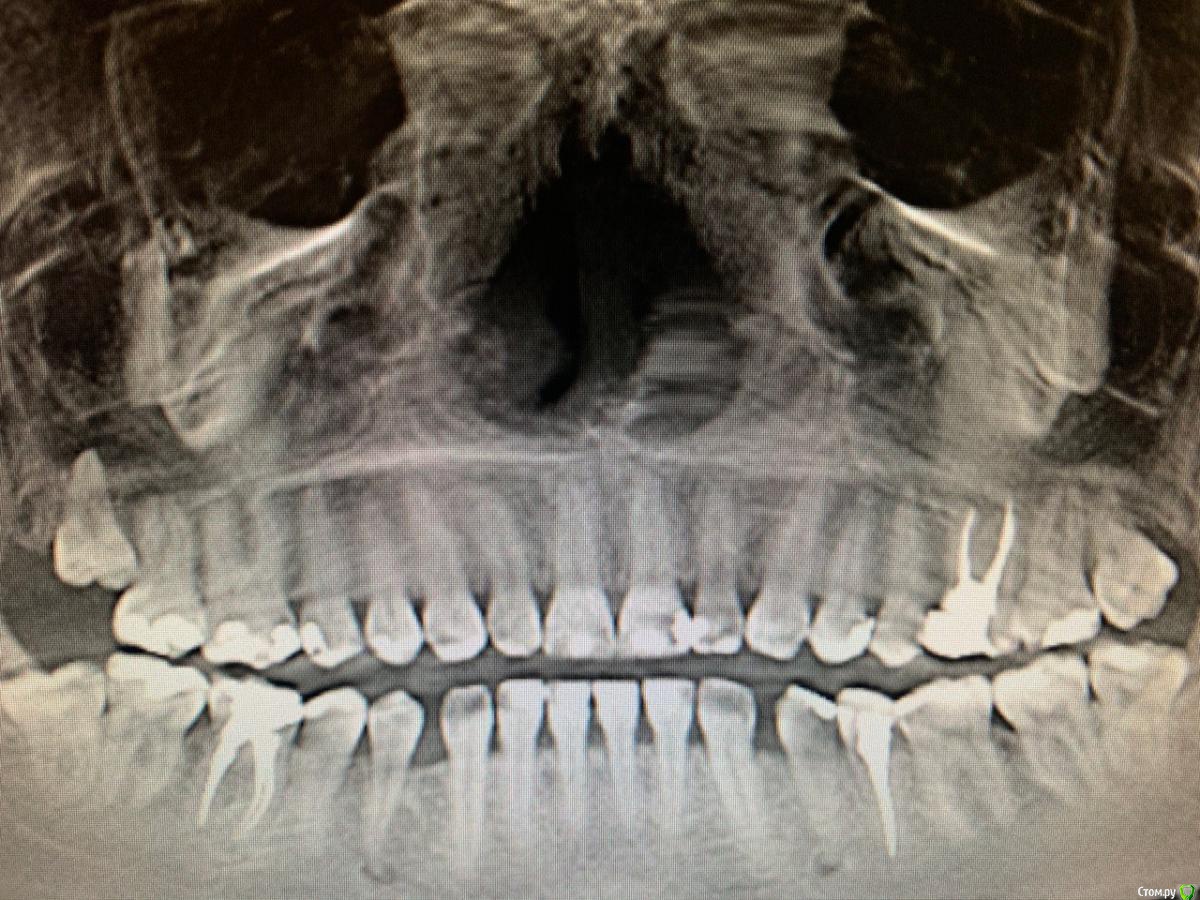

Nataly45 Опубликовано 8 октября, 2019 Поделиться Опубликовано 8 октября, 2019 Добрый вечер, мне очень нужен Ваш совет. Сразу скажу я была в 2 клиниках. и Завтра записала к члх на удаление этой 6 ки. Но очень сомневаюсь В пятницу вечером больно кусать стало, в субботу немного болело(пошла сразу к врачу сделали снимок всей челюсти) сказали надо именно удалять и именно у члх, прописали антибиотик и обезбол. Купила ,начала пить сразу. В воскресенье началась к вечеру приличная боль , о еде и речи не могло быть даже челюсть сомкнуть не могла. В понедельник,чтобы перепроверить первый диагноз удаление пошла в клинику другую,показала им снимок. Там врач предложила попробовать сохранить свой зуб играясь с лекарством,те каждые 2 недели разное лекарство в зуб закладывать,а потом резекцию. Дело это не быстрое но может сохраним зуб и поможет. Но гарантий никаких ,если что удалим. в понедельник началась мега адовая боль,ничего не помогала,звоню первому врачу,сменили антибиотик и обезбол и о чудо, мне стало легче и отлегло. Сегодня целый день не болит. но кусать больно . сказали еще что под зубом киста.Что делать? удалять или попробовать свой сохранить. Спасибо Ссылка на комментарий